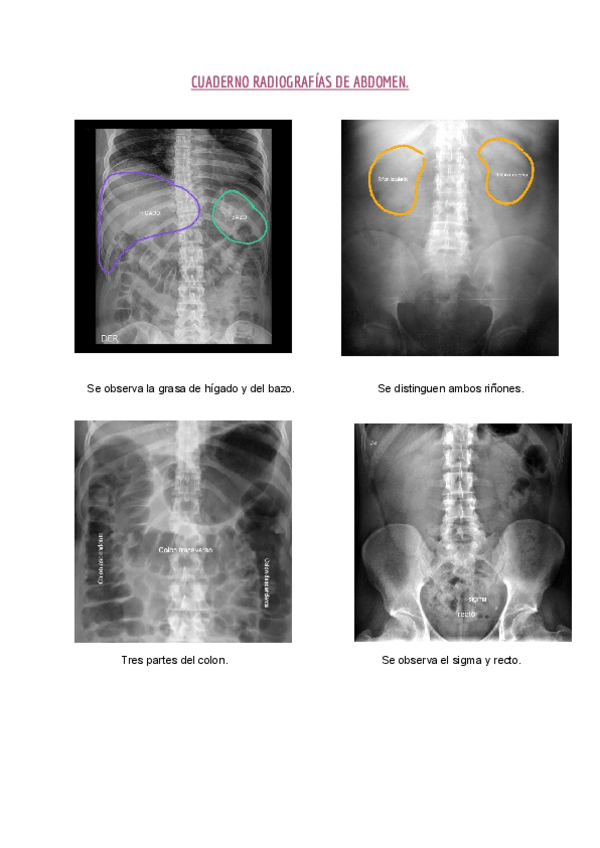

Apuntes - Cuaderno-abdomen-HLC.pdf

3 páginas